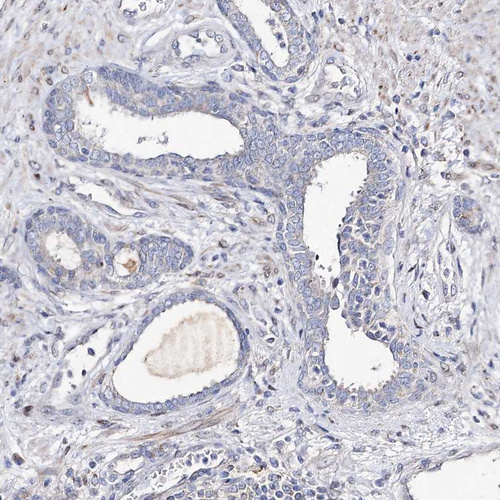

Immunohistochemical staining of human pancreas shows strong cytoplasmic positivity in exocrine glandular cells.